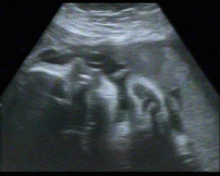

A few weeks ago, Nathalie made the official switch from being pregnant in Ireland (aka, all appointments at her Dublin GP and Holles St) to being pregnant in Lisbon (getting her records, sussing out local hospitals etc). We’ve signed up with a wonderful doula, had our 32-week ultrasound and, after a good 3-4 hours of queues, muddled Portuguese and hardcore bureaucracatic fandangling are registered with our local health centre. Some things are drastically different here (things like blood tests and ultrasounds happen at dedicated centres, not at your doc’s, for example) but all in in all it’s all been fairly doable. Here's a gif of our son or daughter practising swallowing (yes, I know we're already the worst).